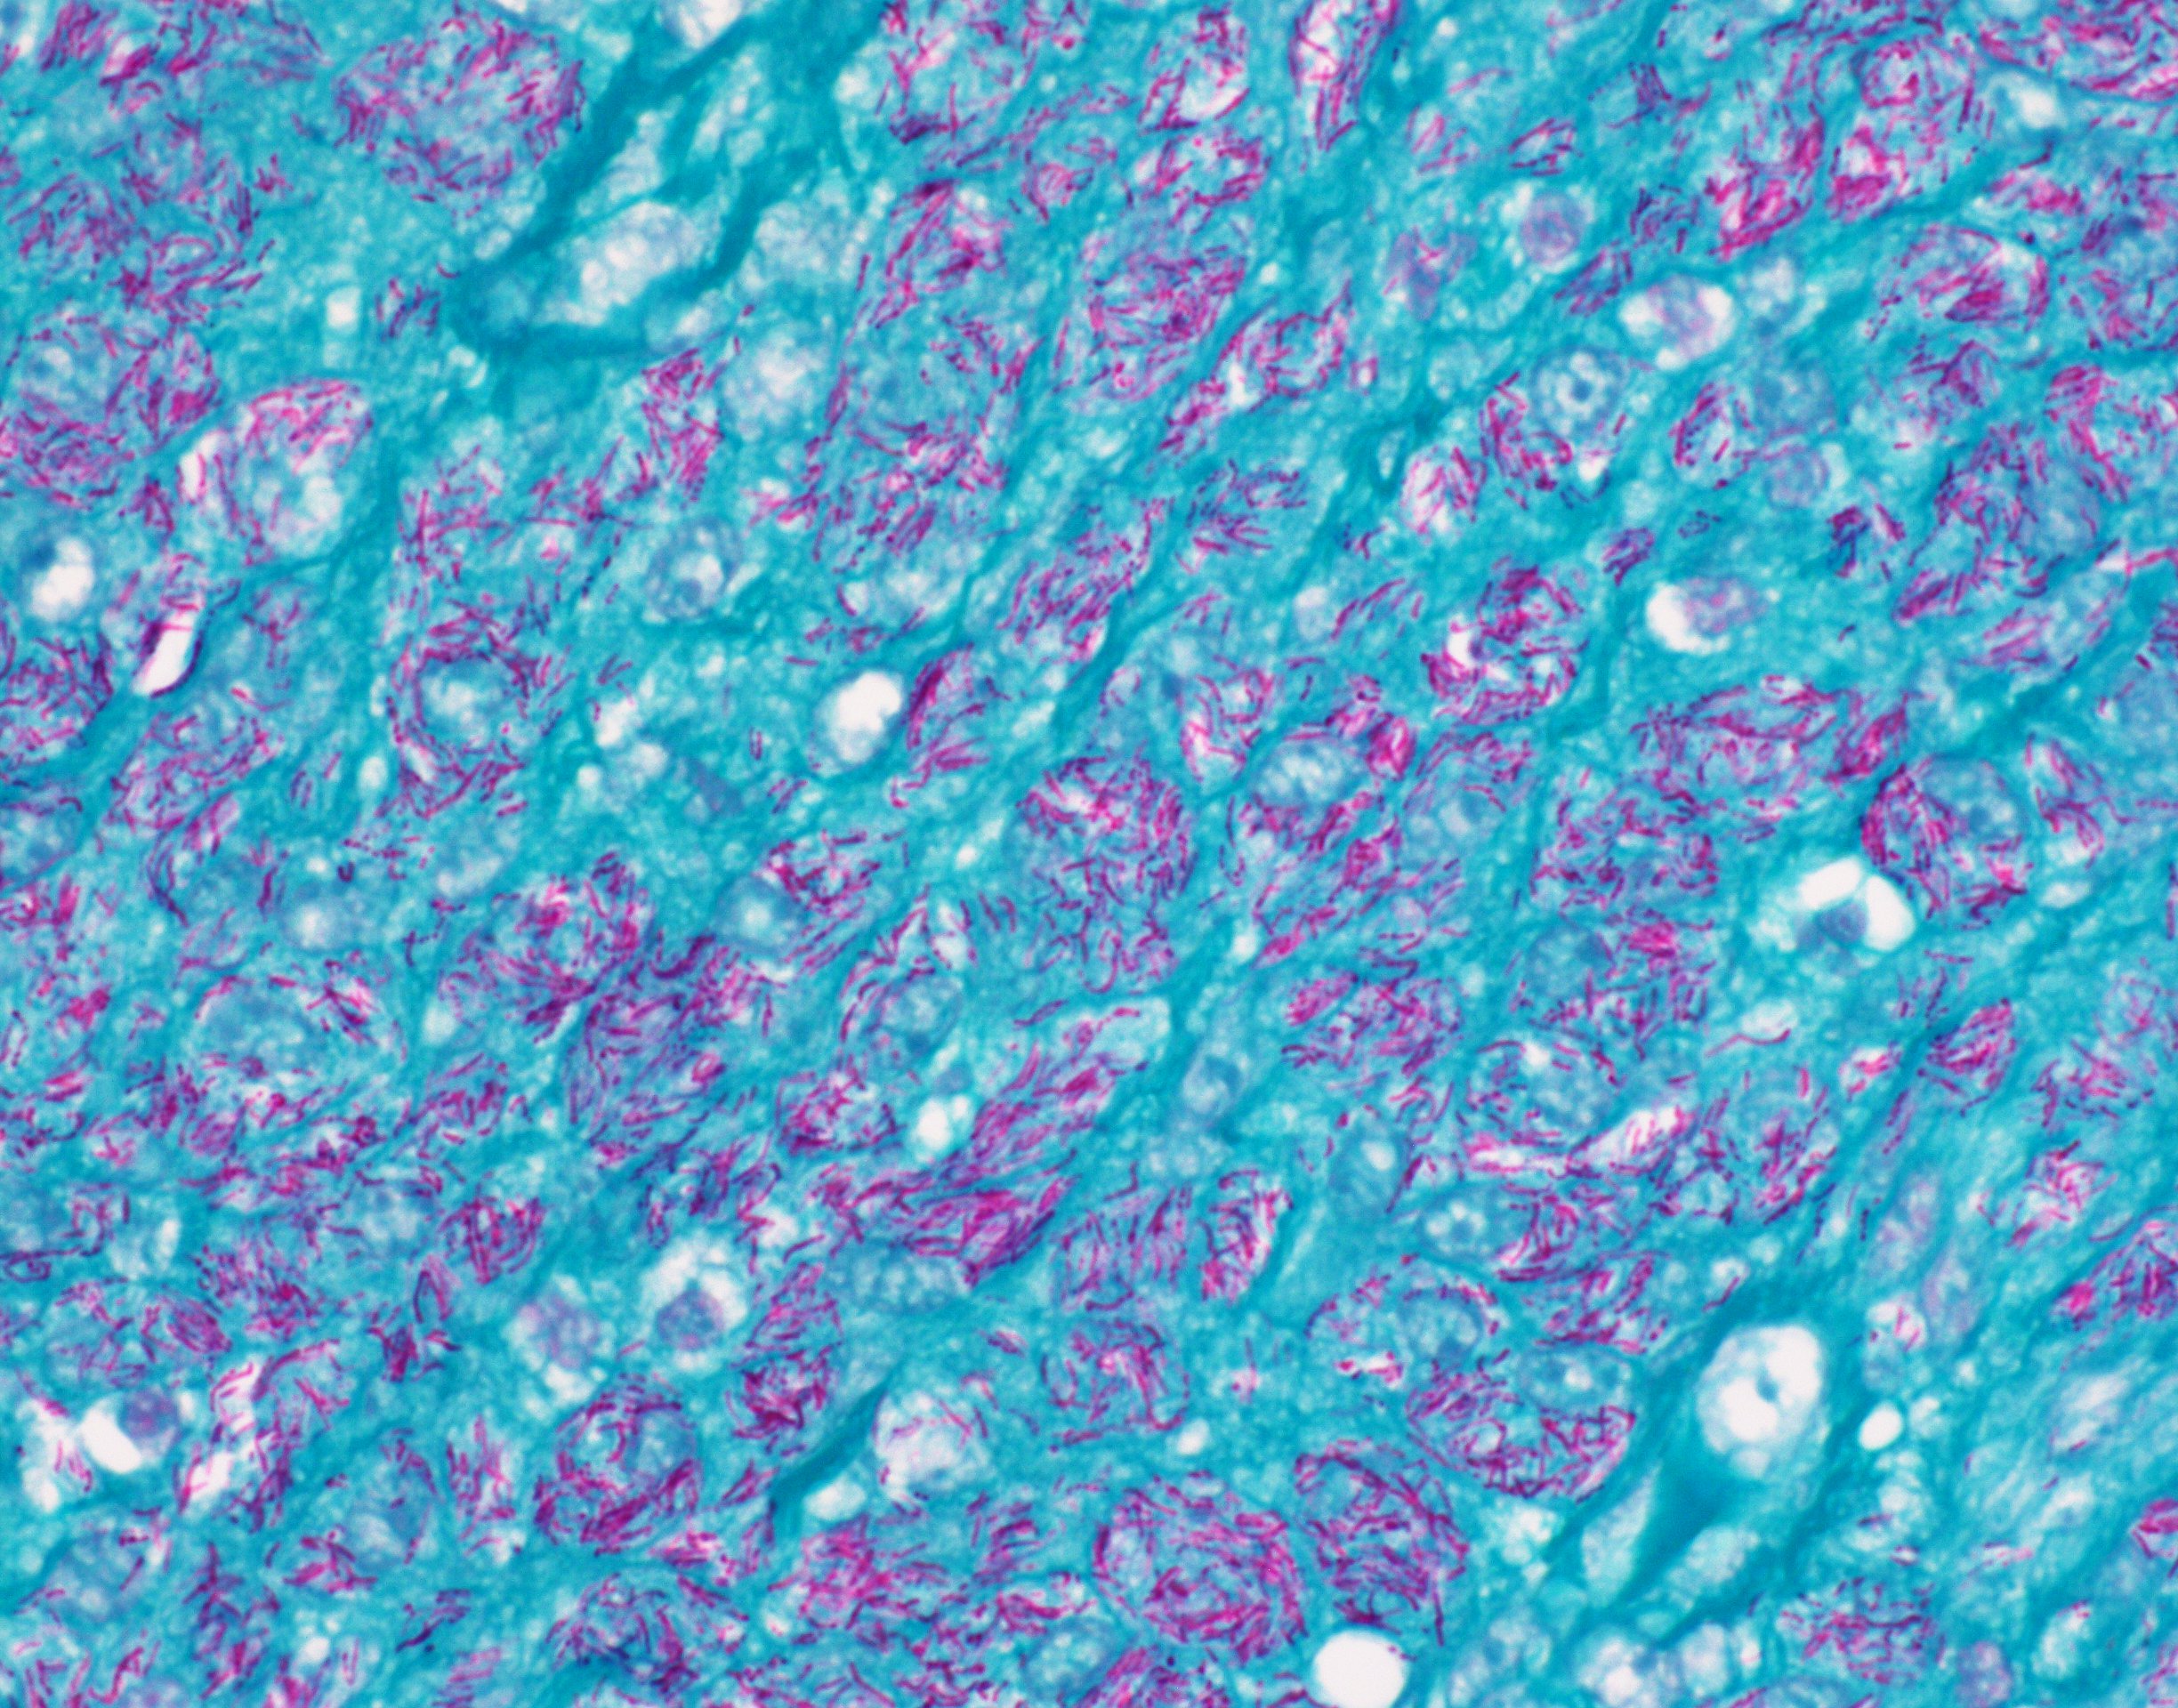

Microscopic (histologic) description

- Nodes show partial / complete effacement by storiform pattern of bland spindle cells, some with vacuoles

- Numerous vessels lined by plump endothelial cells, plasma cells and lymphocytes

- No multinucleated tumor cells, no foamy histiocytes

Microscopic (histologic) images

Contributed by AFIP and Chunyu Cai, M.D., Ph.D. (Case #532)

Positive stains